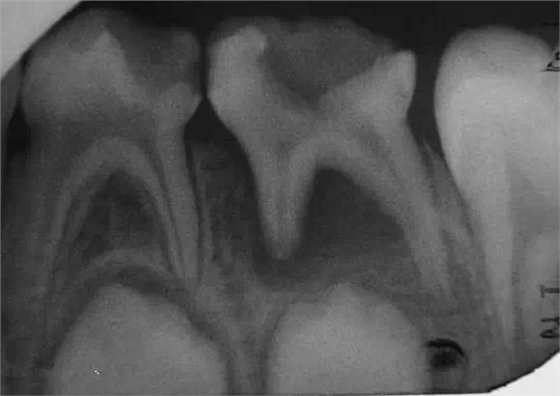

乳牙急性根尖周炎的應(yīng)急處理,首先應(yīng)建立髓腔引流,用快速鋒利的渦輪機牙鉆開髓,開放髓腔,使炎性滲出物或膿液通過根管引流。 (福建醫(yī)大口腔醫(yī)院 高生輝老師的圖片)

已形成粘膜下膿腫的還需在口腔內(nèi)的腫脹部位做局部切開排膿,而腫脹嚴重者,則需用碘仿紗條進行引流。(醫(yī)大口腔醫(yī)院 高生輝老師圖片)

(以上圖片引用自福建醫(yī)大附屬口腔醫(yī)院兒童科 高生輝老師的課件,非常感謝?。?